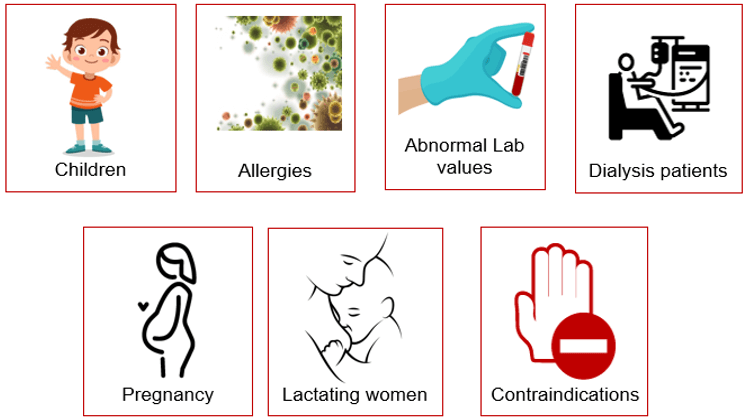

Contraindications

A contraindication is a condition or circumstance that would preclude the use of a CT scan with radiation OR the use of a contrast agent.

Relative or Absolute

An absolute contraindication is a situation that makes a particular treatment or procedure absolutely inadvisable. Relative contraindication means that caution should be used when two drugs or procedures are used together.

For children and elderly patients, the contrast clearance is low. It is important to perform lab analysis prior to any injection of contrast media to verify that renal failure will not be an issue.

Certain patients are considered high risk and pose additional concerns when using contrast media.

Great care must be used when injecting iodinated contrast to certain patients. Contrast-induced nephropathy otherwise known as deteriorated kidney function as a result of iodine-based contrast can have serious effects. Increased morbidity, as well as mortality rates, have been demonstrated in patients at risk. Those patients can include heart patients, diabetics, the elderly and those with known poor renal function and abnormal lab values. Certain precautions should be taken with gravid (pregnant) and lactating women.

Pregnant Women

CT examinations may be contraindicated in patients who are pregnant or suspected of being pregnant unless the procedure benefits out way the risks to the mother and the fetus. When possible an ultrasound should be used. If not possible, or in the case of trauma, a CT scan can be performed with the fewest slices and lowest doses possible to reduce the fetal dose. Always consult a radiologist prior to the examination. Gravid patients pose 2 main problems:

Breast-Feeding Women

Allergies